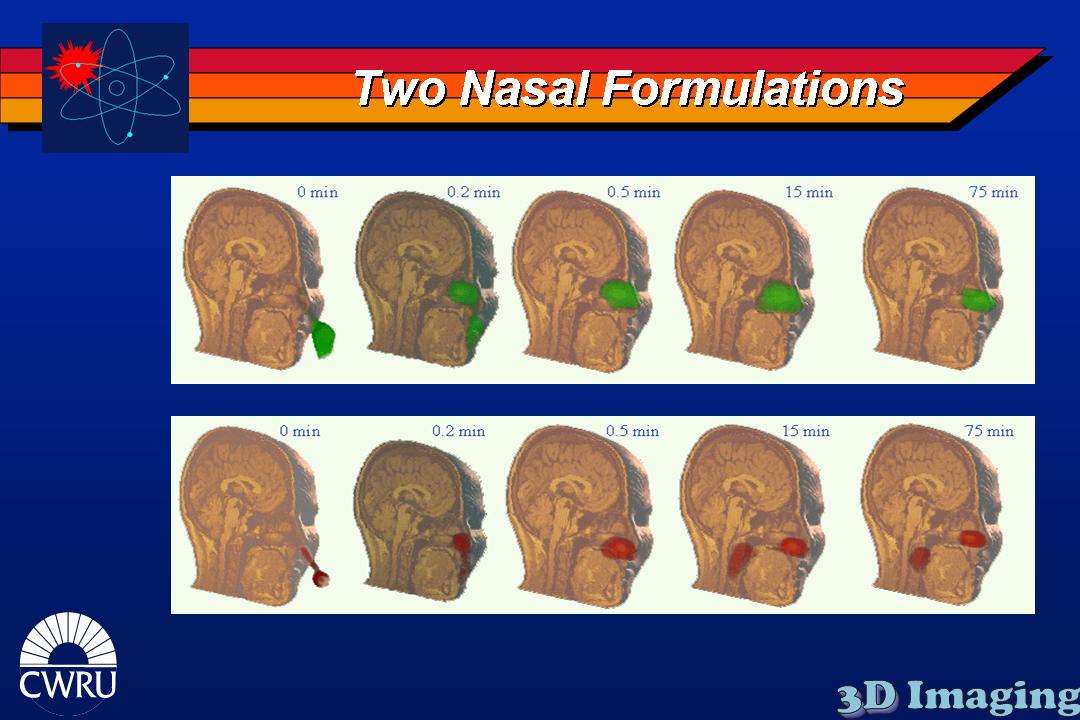

Several inhaled drug formulations were studied by radiolabeling the active ingredient (several different steriods) with C-11 or F-18, formulating that ingredient as the dosage form (different MDI, DPI, and nebulizer formulations), and performing quantitative PET studies of the regional biodistribution and kinetics.

Click on images to see additional examples, larger versions, and videos.